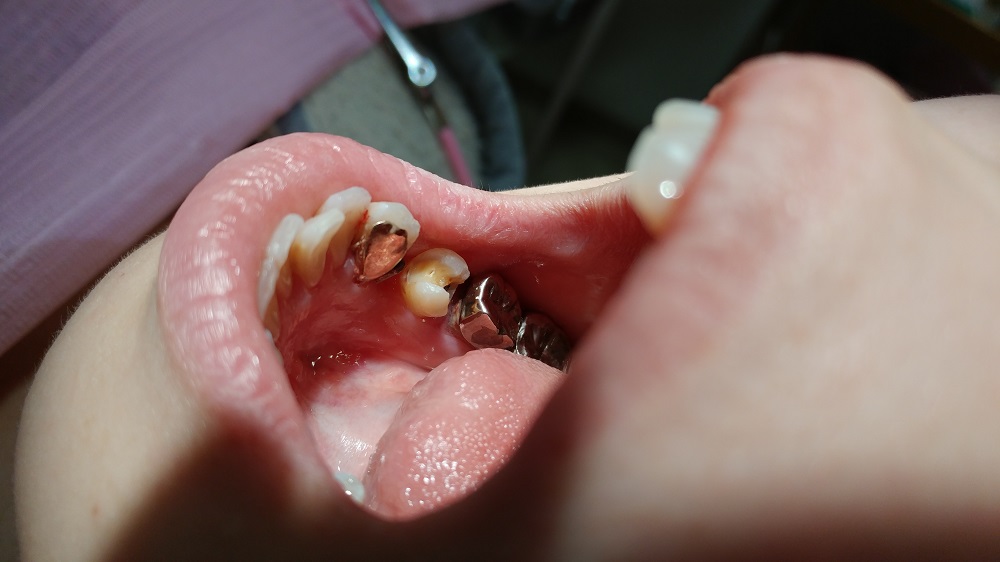

患者さんは顔出しNGだが、写真の掲載も了承してくれた

これが、抜歯した後の状態である

奥の歯には金属の詰め物(インレー)と白いレジンの詰め物が施してある

素人では判りづらいだろうが、近心側 解りやすく言えば、抜歯した1つ奥の歯の歯を抜いた側には白いセメント「レジン」が詰まっている